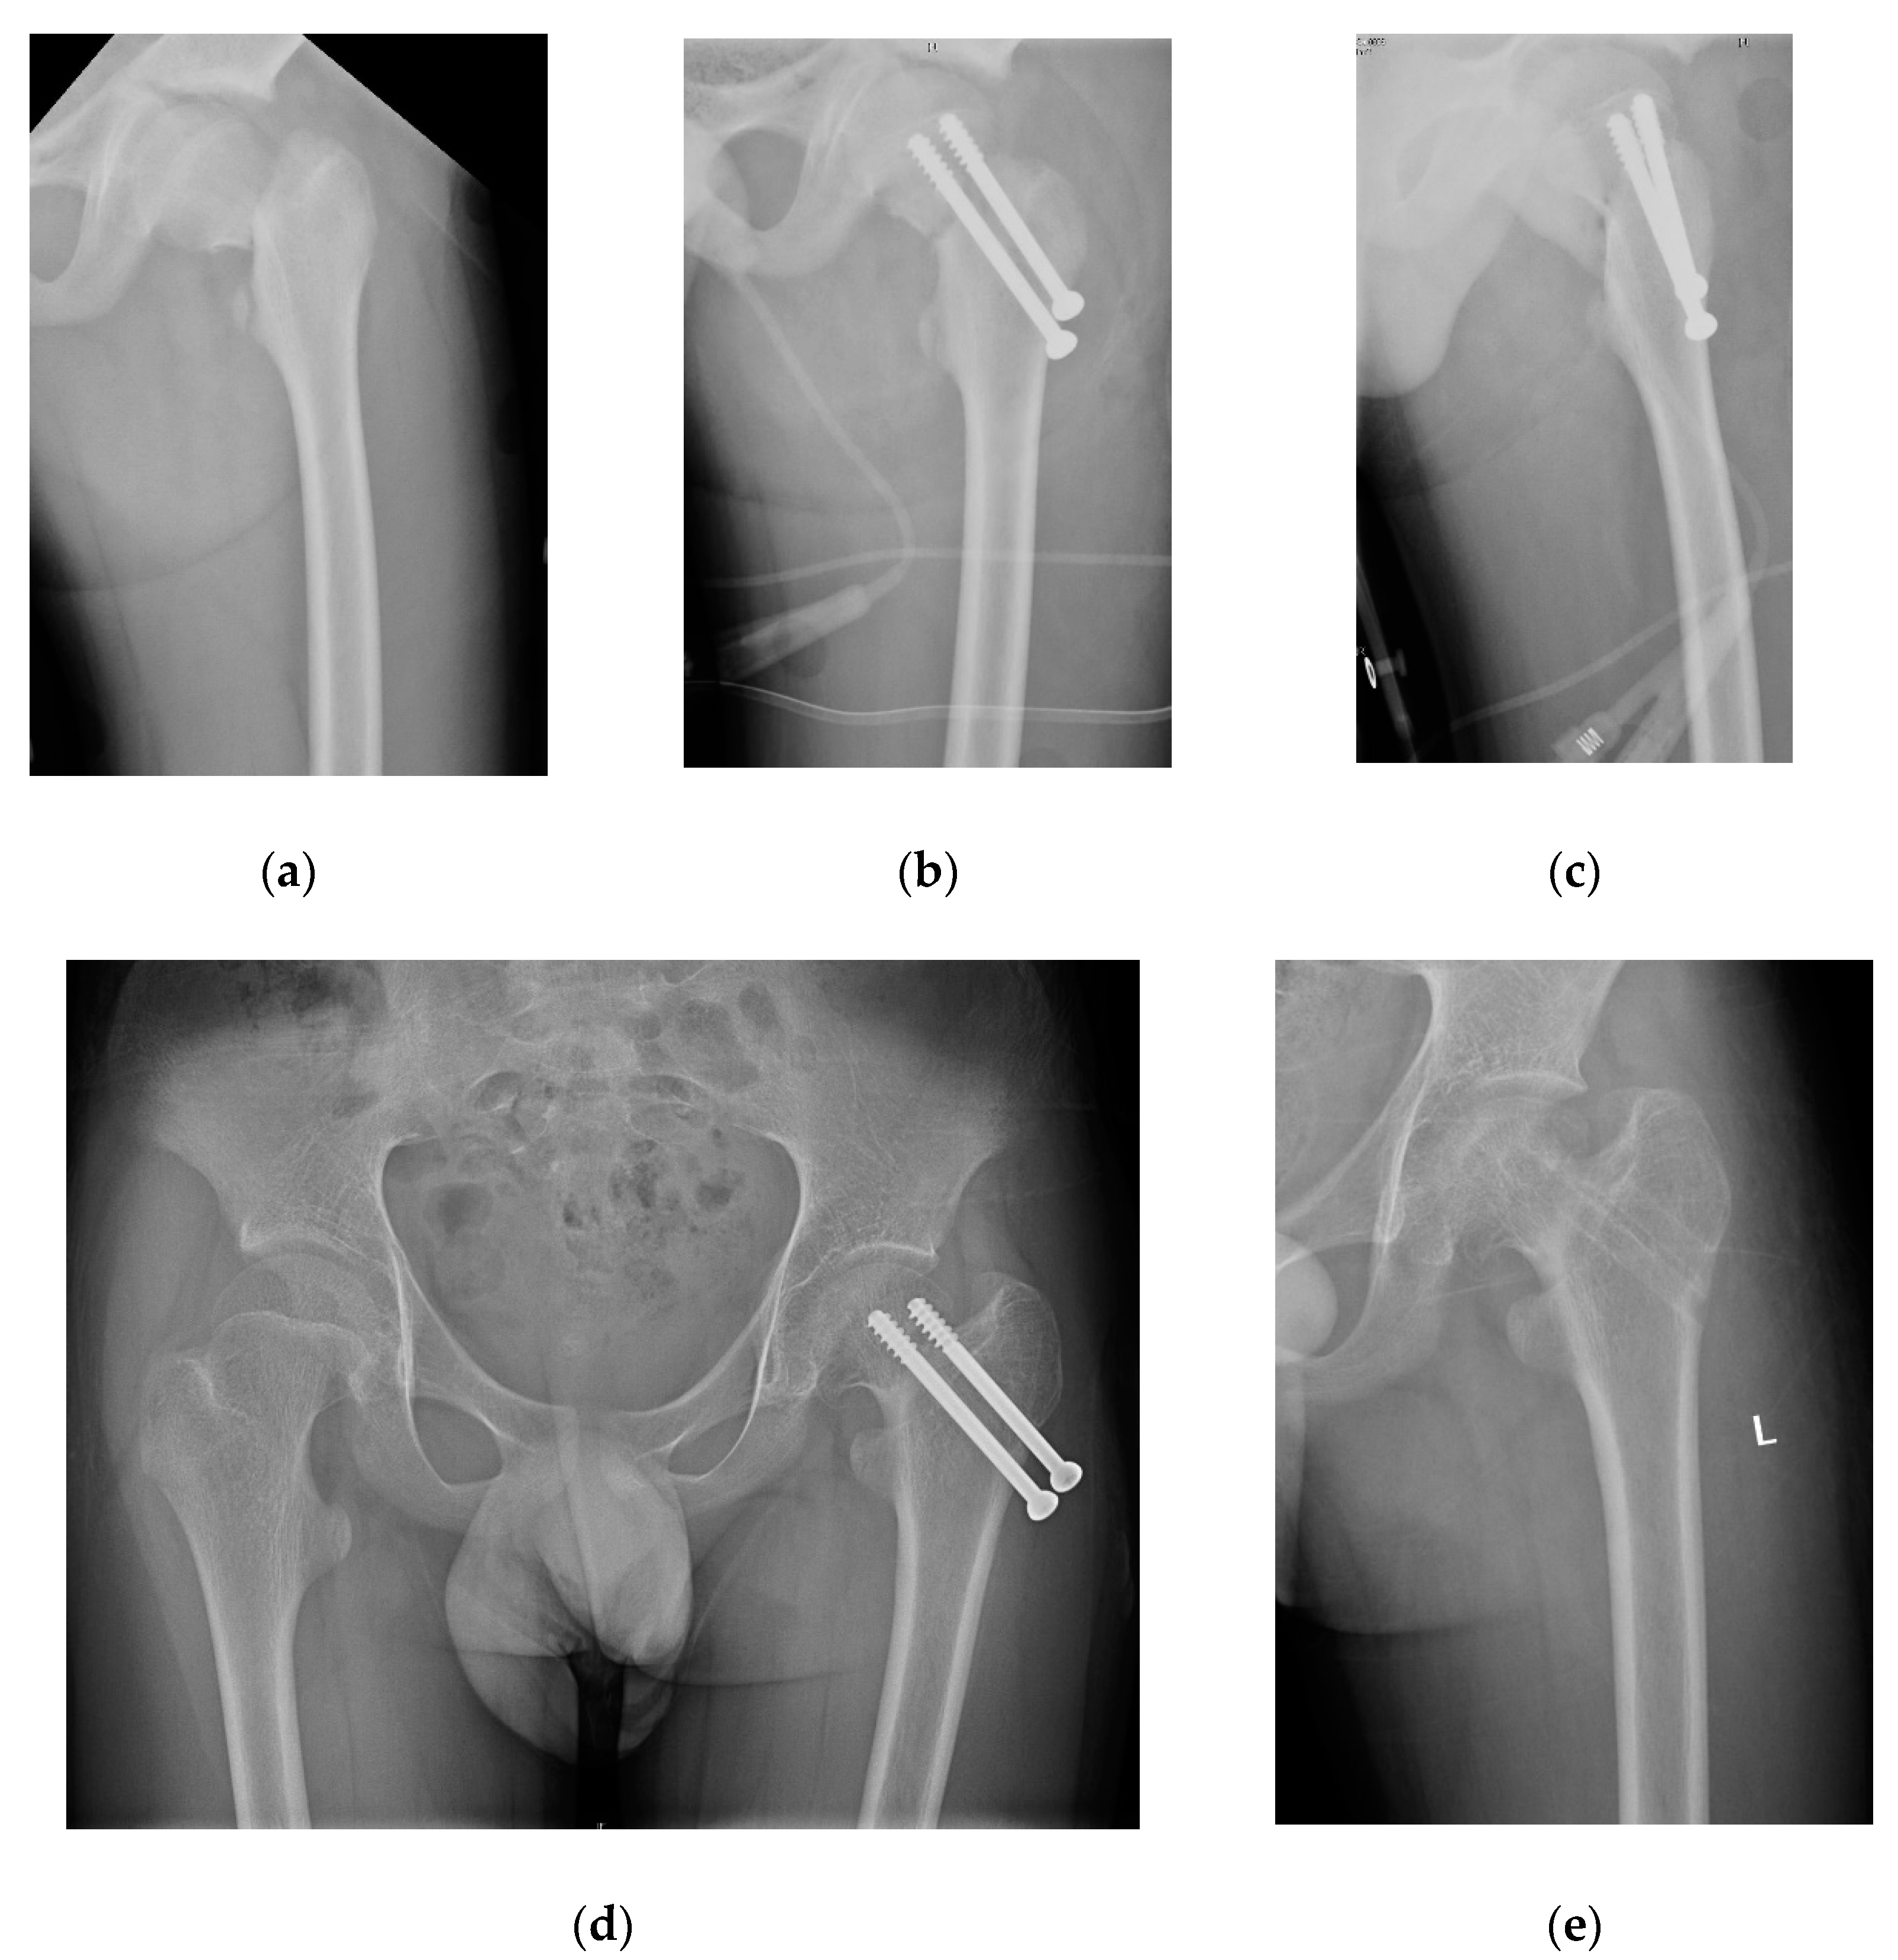

2.4. Cannulated Compression Screw